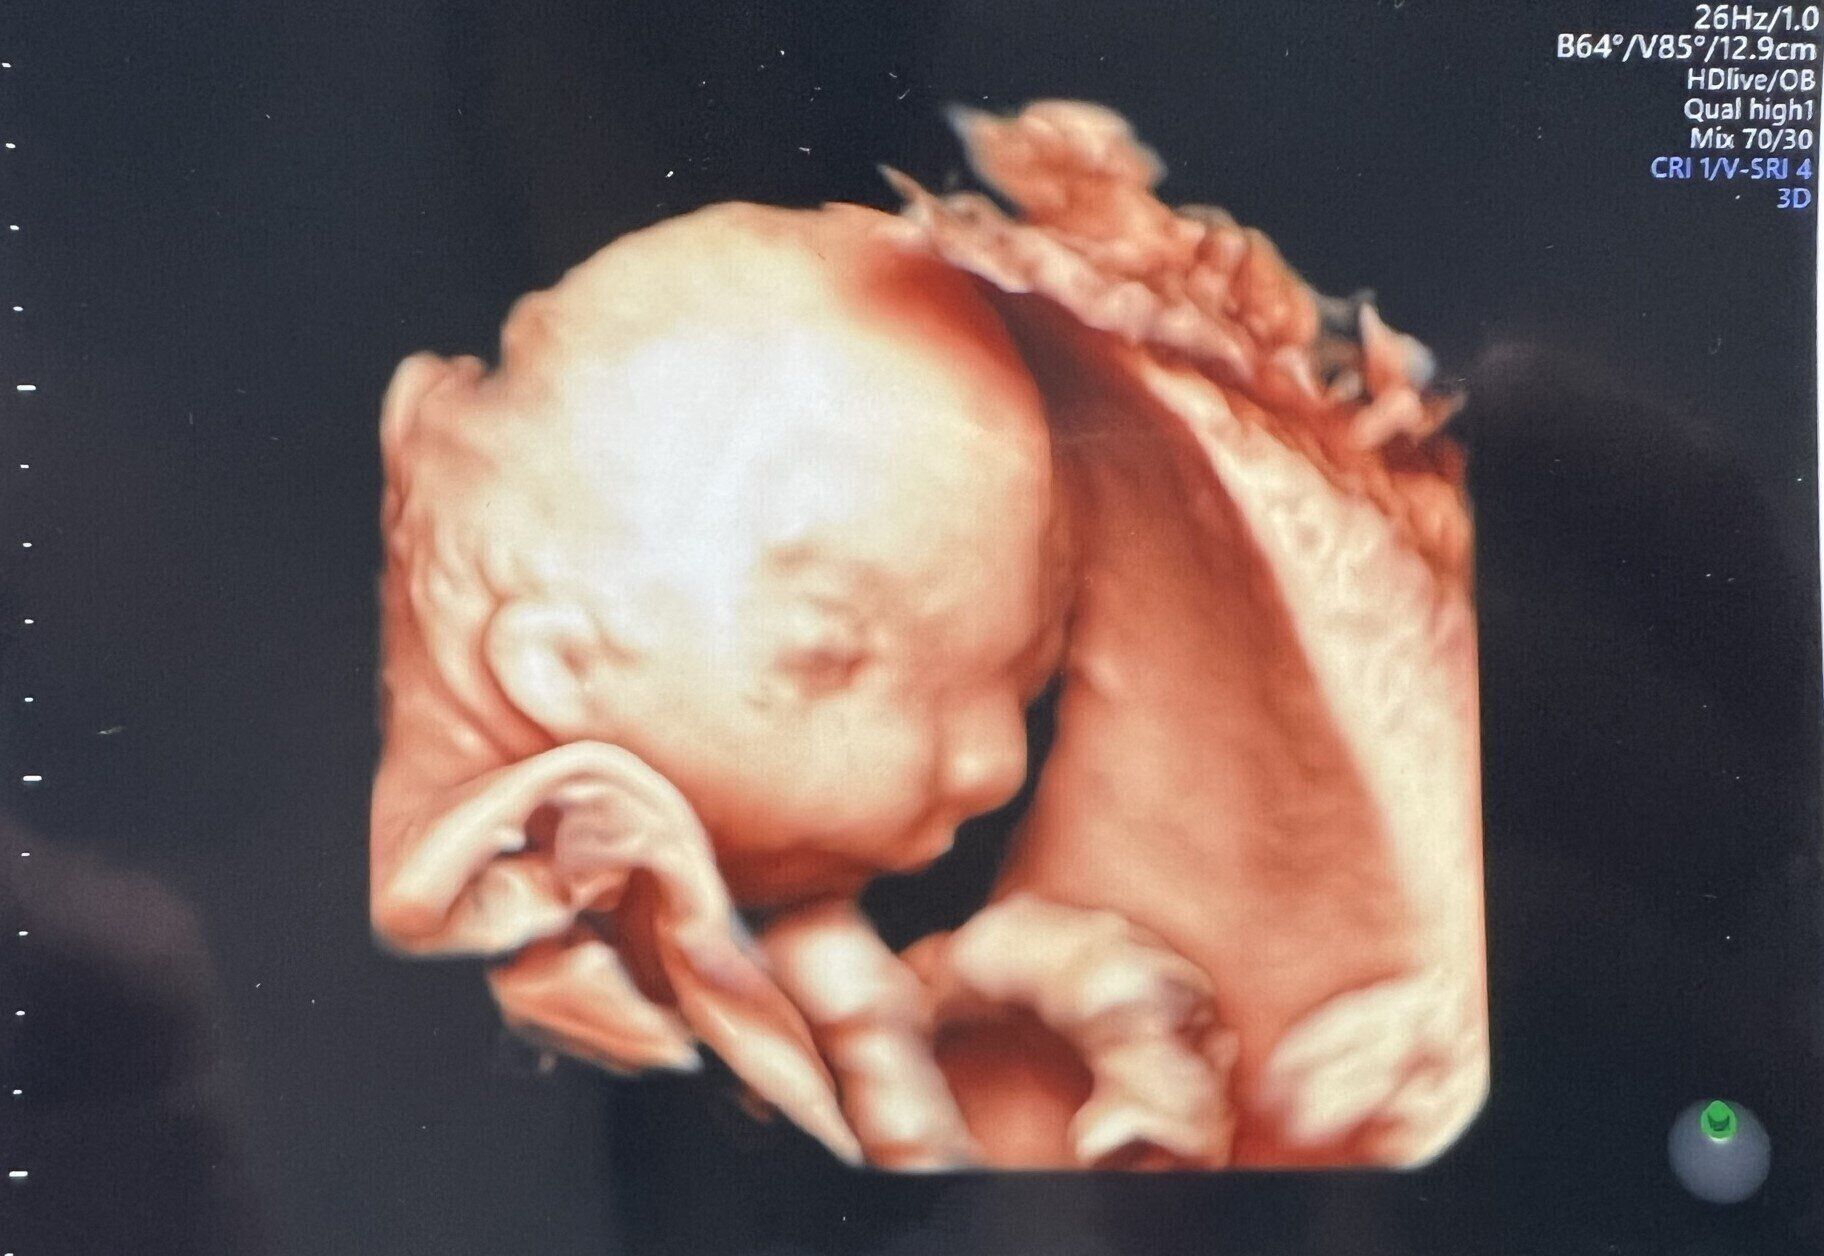

エコー写真を見せてもらったところ、目の間隔も広そうで、それぞれの目が顔のはしっこについているようにも見えました。そして眼球の位置とまぶたの位置がちょっとずれている可能性があるとも指摘されました。

しほ 先生も、実際に生まれた赤ちゃんを見てみないとどんな状態なのかわからないとのことでした。そのときは、斜視のような感じなのかな?と考えていました。